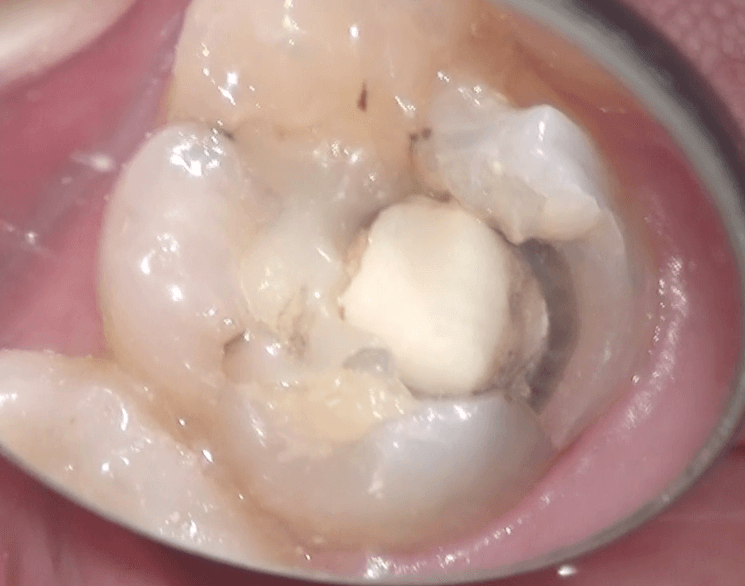

患者さんは30代の男性で、左上の奥歯が欠けた、とのことで来院されました。見てみると・・・

左上6が欠けていて、その歯にはコンポジットレジンがつまっており、下のほうが黒くなっていて、虫歯になっていることが疑われました。問診、歯髄電気診、冷刺激診を行い、神経は通常の状態であると診断し、治療を開始しました。ここが、実はポイントで、もし、虫歯が深く、神経が外側に露出しそうになった場合に、歯髄がどうなっているのか、術前に診断しておかないと、歯髄保存療法ができるのかどうかがわかりません。この、術前の診断をするかどうかが、専門Dr.とそうでないかの違いだと思います。専門Dr.とそうでない人の大きな違いは腕ではありません。このように、術前にきちんと診断し、患者さんにわかりやすく説明できるかどうか、だと思っています。